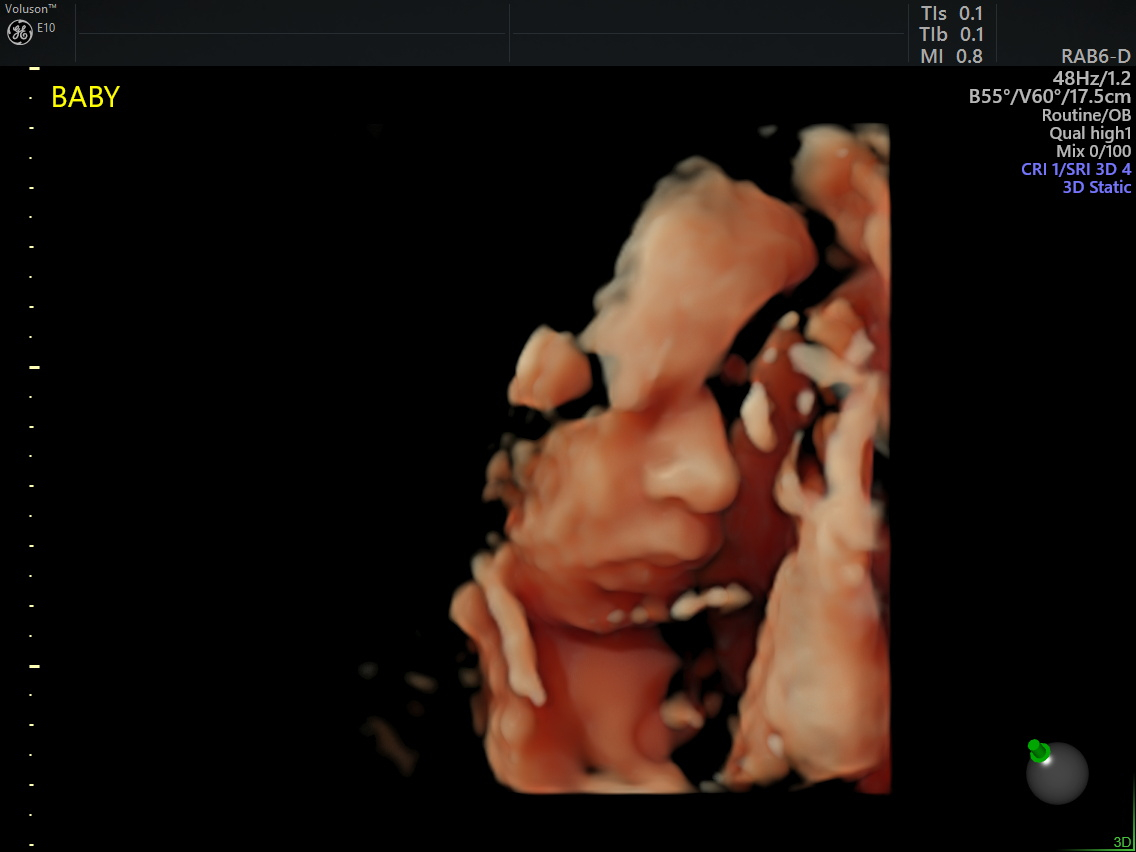

19+4! We got the results yesterday, Baby is healthy, no concerns, no abnormalities! It was amazing to see Baby moving around, we saw knees and hand bones, he/she rubbed their eyes and wiggled around. Last time Baby was sleeping so seeing him/her move was really special. So excited!!!